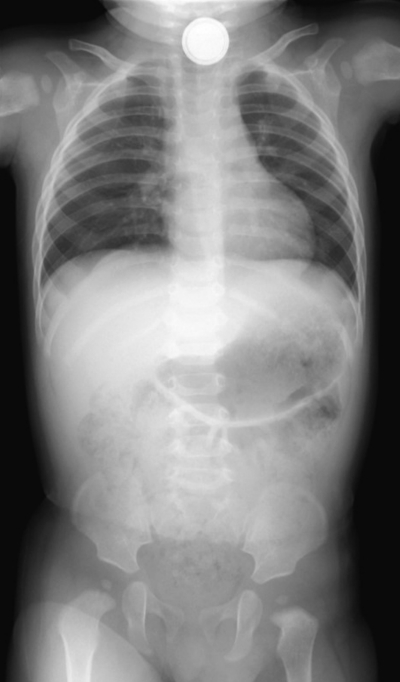

搬入時には児の機嫌は良く、顔色は良好である。努力呼吸を認めず、呼吸音に異常を認めない。18時30分に撮影した胸腹部エックス線写真を別に示す。緊急で内視鏡的摘出術を行うこととした。

電池誤飲症例。電池は腐食作用が強いため即座に摘出する必要あり。